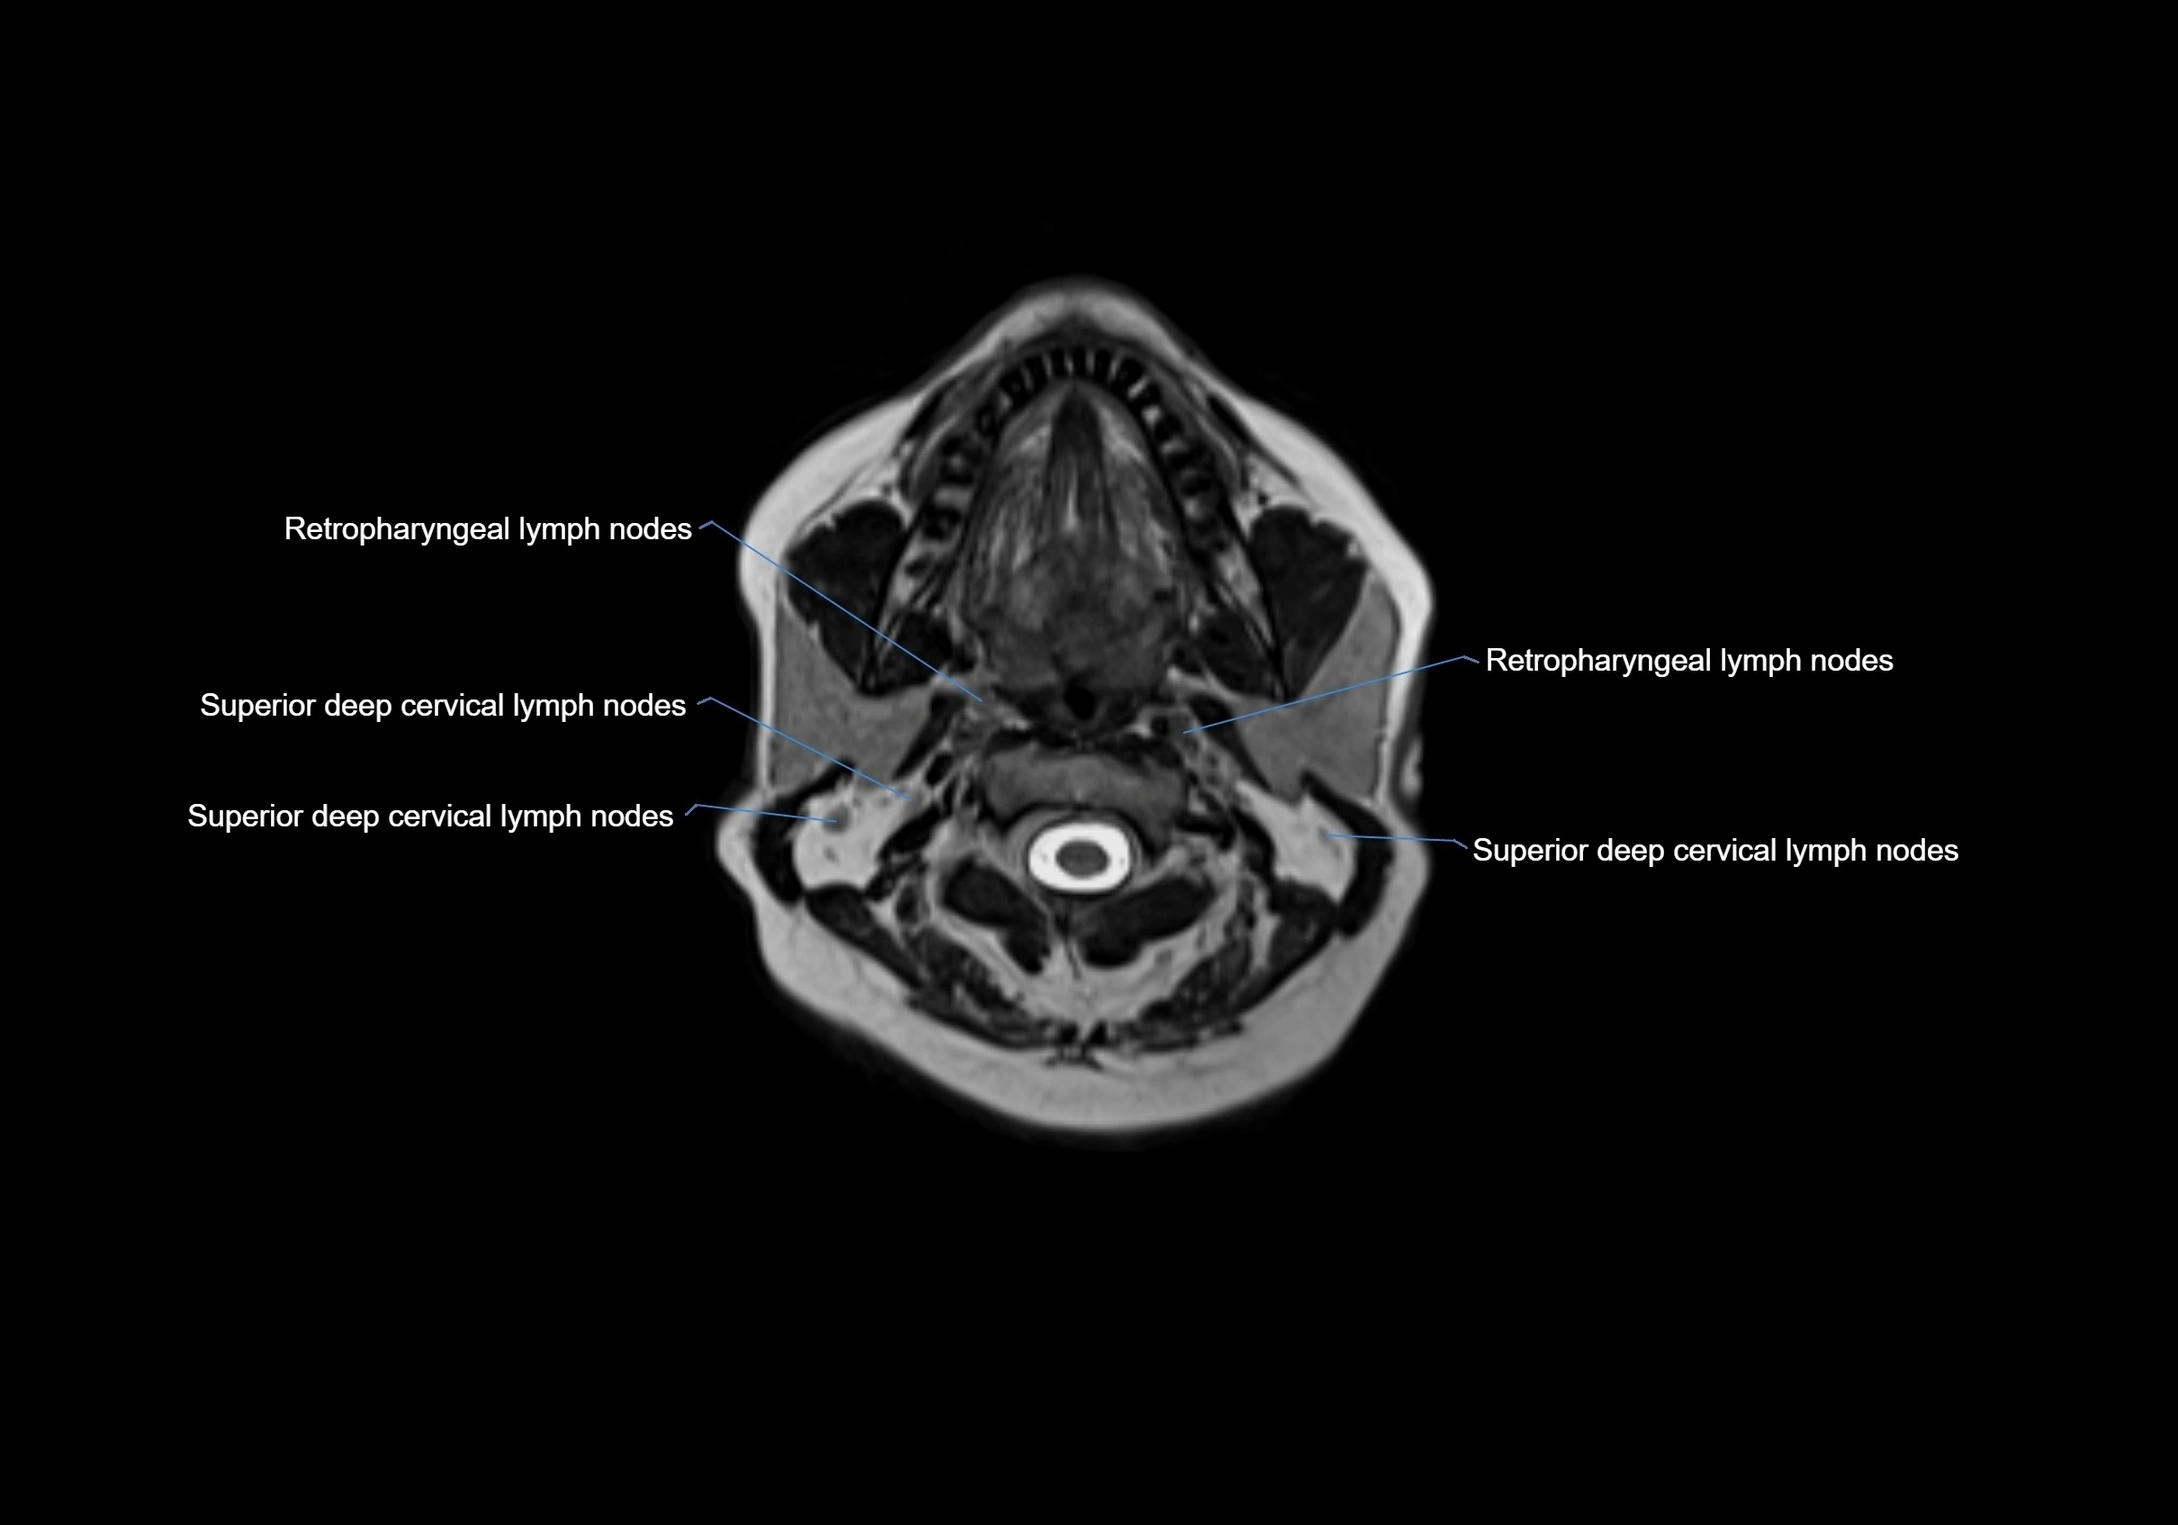

MRI images

image